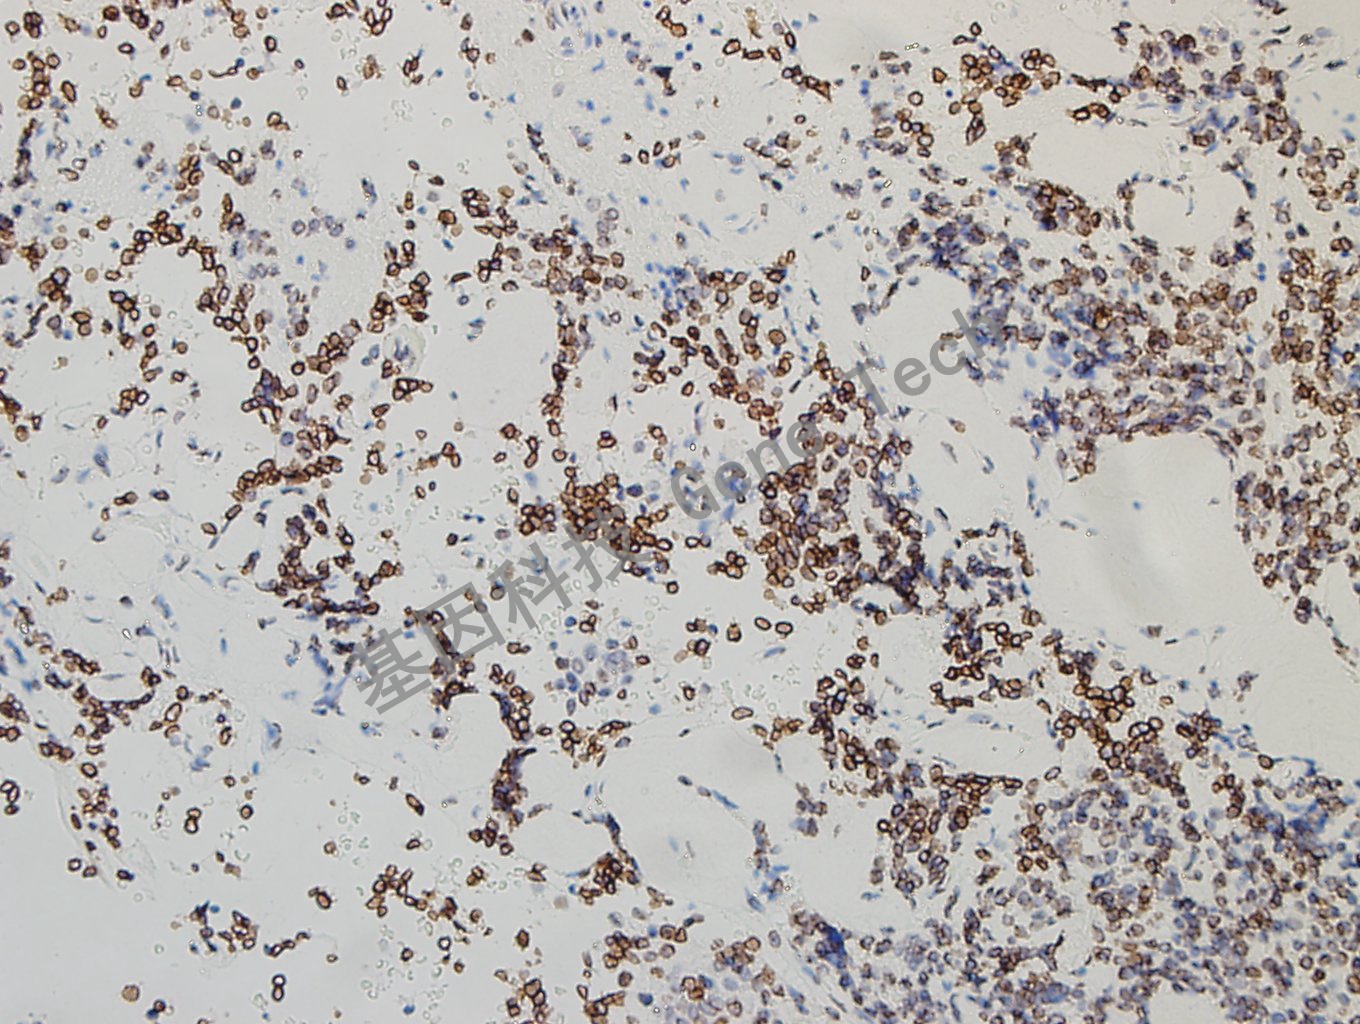

肺癌石蜡切片,用 GATA2(GT2320)染色,细胞核阳性,DAB 显色。